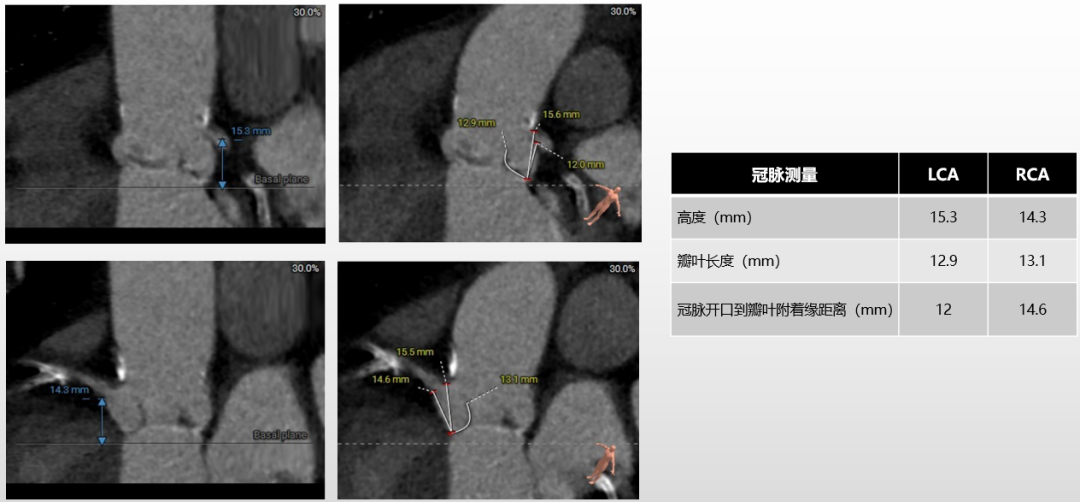

冠脉评估:

左右冠开口高度良好,左冠切线位瓣叶长度>冠脉开口到瓣叶附着缘距离,右冠切线位瓣叶长度<冠脉开口到瓣叶附着缘距离;左右冠脉均可见弥漫性钙化。